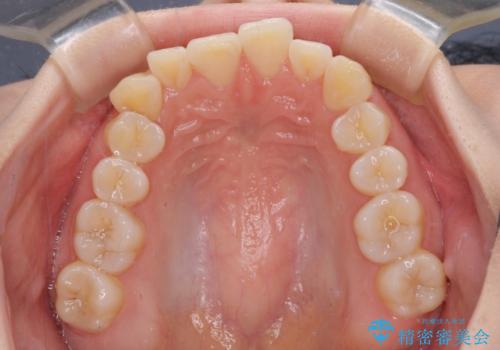

- 上下前歯のデコボコを気にして来院された患者様です。

ワイヤー矯正でもインビザライン矯正でも対応可能でしたが、インビザラインでの自己管理の煩わしさを避けるため、ワイヤー装置にて矯正治療を行うこととしました。

患者様も驚く、僅か10か月での治療終了となりました。

下顎前歯が1歯欠損しているため、上下正中は合わず、左右奥歯の咬み合わせは理想的とはならない仕上がりとなります。